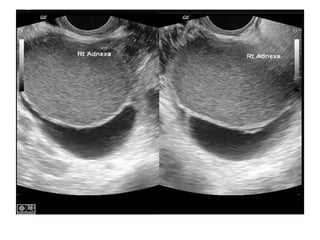

• Imaging: US of the pelvis and abdomen

(transvaginal US) is of limited value in the

diagnosiis of early pelvic endometriosis.

• In advanced disease where endometrioma

and pelvic mass are present pelvic US

produce typical images.

Ultrasonography

• Endometriotic cysts (oval or round)-

capsulated fine homogenous, uniform,

granular echoes, anechoic, single or

multiple, unilateral or bilateral

• On doppler: no vascularity within the mass

• Ovarian adhesion to uterus

• Free floating fimbria or

sonosalphingography